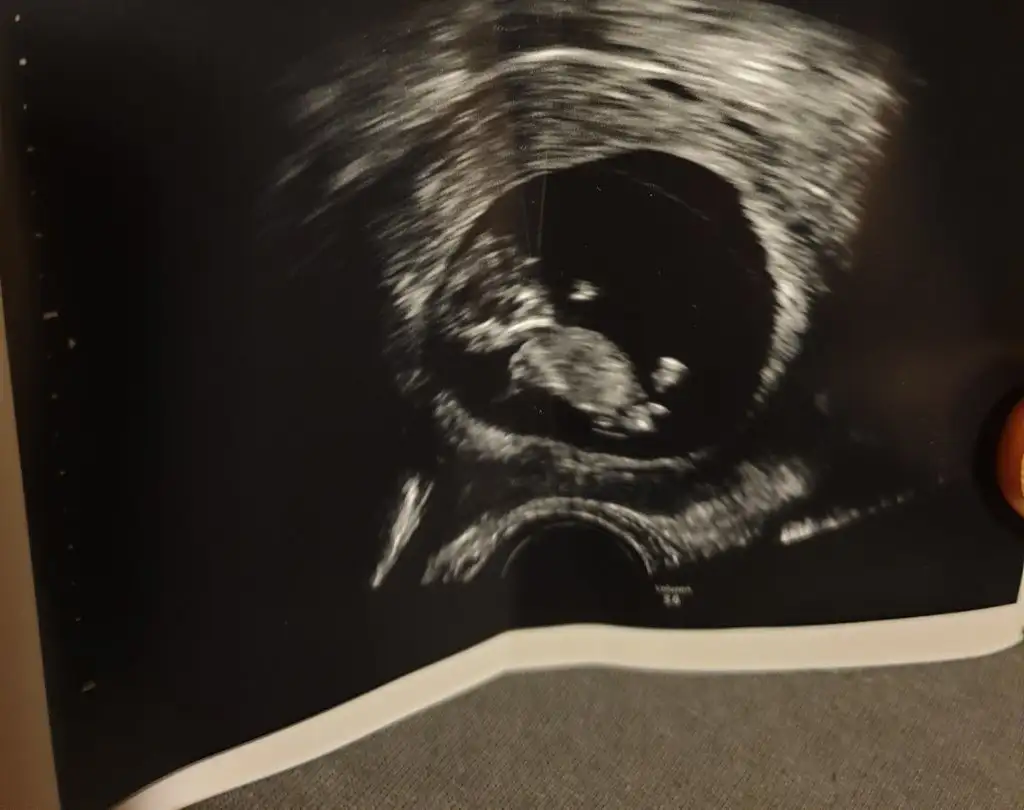

Merhaba 11+4de size usg atmıştım kız gibi demistiniz şimdi 14+5 atıyorum tekrar yorumlarmısiniz hala söylemedi doktorErkek görünüyor

Ay ben ikra kadar anlamam ama kız gibi geldi yaMerhaba 11+4de size usg atmıştım kız gibi demistiniz şimdi 14+5 atıyorum tekrar yorumlarmısiniz hala söylemedi doktor

11+4 de kız demiştim ama 14+5 de artık organı oluşmuş oluyor bakalım hayırlısı olsun tipi kız gibiMerhaba 11+4de size usg atmıştım kız gibi demistiniz şimdi 14+5 atıyorum tekrar yorumlarmısiniz hala söylemedi doktor

Teşekkür ederim doktorda ben kız diyorum ama emin değilim dedi netlesince yazicam size11+4 de kız demiştim ama 14+5 de artık organı oluşmuş oluyor bakalım hayırlısı olsun tipi kız gibi